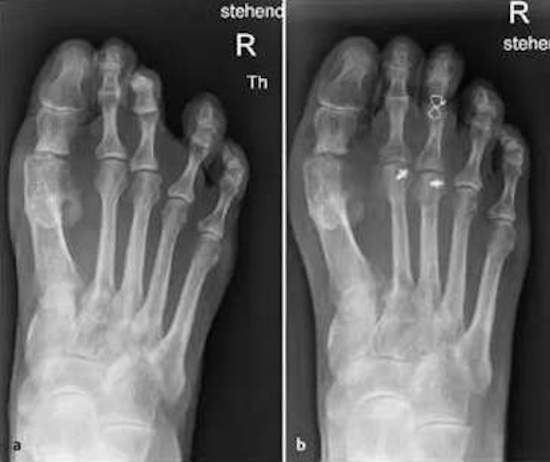

a) Beugefehlstellung des PIP III Gelenks bei Extensionsfehlstellung im MTP II und III Gelenk b) Postoperatives Röntgenbild nach Weil Osteotomie II/III und PIP III Arthrodese